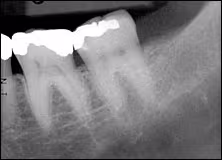

A periapical film of the left mandibular molars adjacent to the ulcer was not contributory. (Figure 3) An occlusal film showed a localized opacity contiguous to the lingual mandible in the area of the ulcer. (Figure 4)

Figure 3. Periapical film of left posterior mandible; no bone anomalies are evident.